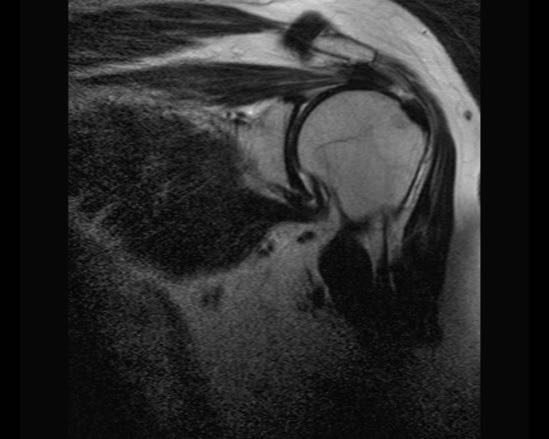

Rách toàn bộ chiều dày hoàn toàn

Nhấp vào hình ảnh để phóng to, sau đó cuộn qua các lát cắt.

Có hình ảnh rách toàn bộ chiều dày gân cơ trên gai kèm co rút và teo cơ.

Lưu ý các dải mỡ trong cơ tròn bé, cơ trên gai và cơ dưới gai.